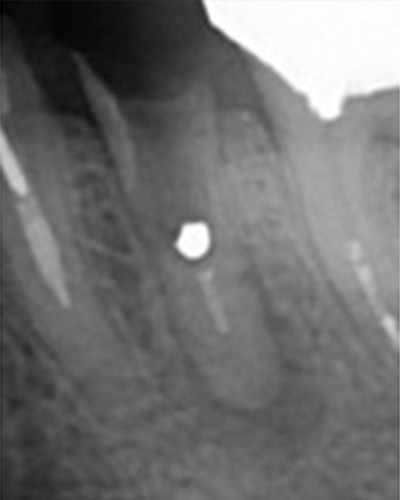

突き出たガッタパーチャポイントと大きな病巣

なぜか根管途中から突き出たガッタパーチャポイント